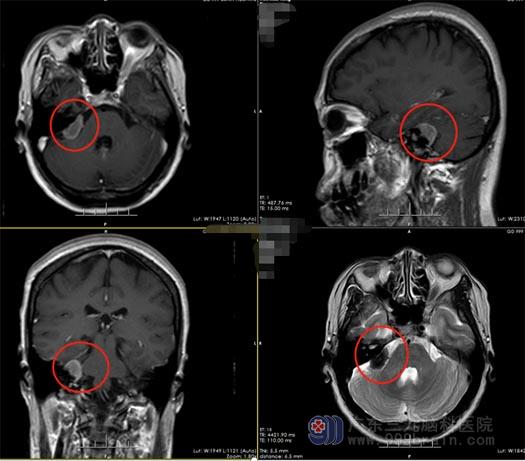

华大姐的进一步影像学检查发现:右侧桥小脑角区占位性病变凸入右侧内听道,考虑脑膜瘤的可能性大。王国良主任告知:这类肿瘤都是缓慢生长的,当肿瘤体积比较小的时候病人一般是没有症状的,随着肿瘤体积逐渐的增大,肿瘤会对周围的解剖组织进行压迫,在这个区域最多见的神经就是面听神经、三叉神经和后组颅神经,深方和背侧是脑干和小脑,早期的非特异性表现是头晕、头胀、头疼,走路不稳等情况。继续进展会表现出相应的颅神经的症状,最为多见的是脸麻、张嘴困难、面部的疼痛,面听神经受到肿瘤的干扰,病人会表现出耳鸣,进而会表现出听力下降,随着病程进一步发展,病人会表现出面瘫,若后组颅神经受到肿瘤的推挤、压迫和干扰,病人会表现出声音嘶哑,饮水呛咳,这些症状的进展不是突发的,都是缓慢的。华大姐说:我走进医院的时候已经想过各种可能,来这里为了做手术。

▲术前